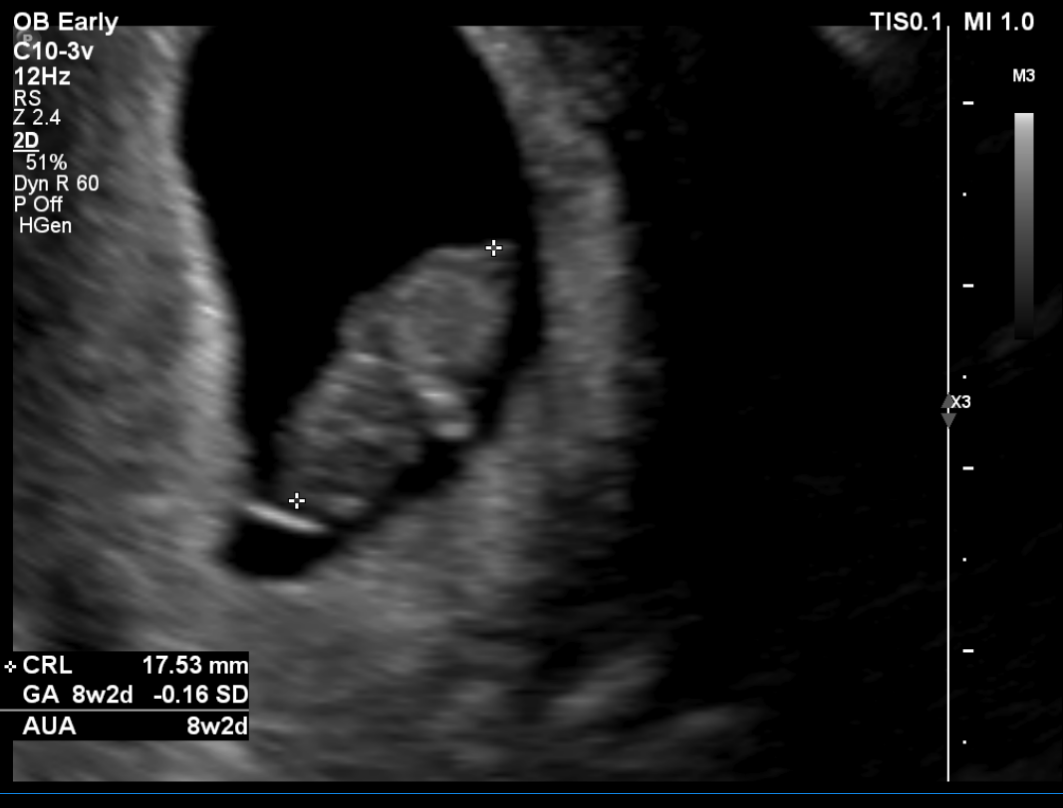

임신 8주 차 초음파 검사 ( 8주 5일 차 초음파 사진)

첫 트롱이 사진 짜잔~~ 젤리곰 이다 >. < 주수에 맞게 잘 자라고 있는 트롱이~ 심박수도 176 bpm으로 정상!

사실 초음파 검사 당시엔 아기 모습을 보지 못했어요~ 검사해주는 분께서 화면으로 보여주지도 않고 아무 말 없이 혼자 보면서 검사를 하시더라고요~ 그래서 저희 남편만 화면으로 확인하면서 너무 귀엽다고 잘 자라고 있다고 ㅠㅠ 저를 안심시켜줬습니다.

검사가 끝나고 전 메일로 받은 초음파 사진으로 처음 우리 아이를 봤어요~! 보고 나서 너무 귀엽고 제 뱃속에 이 작은 생명이 있다는 게 너무 신기해서 울었어요~ ㅜ.ㅜ~ ㅋㅋㅋ